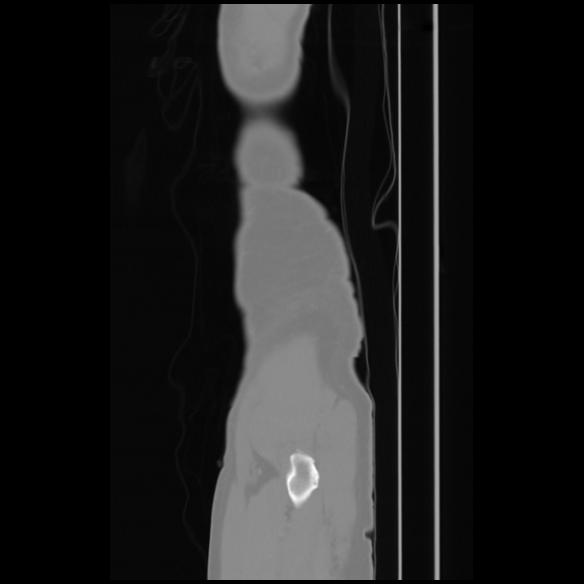

7 CUERPO,CE,Sagittal,3.000,CUERPO,Sagittal,